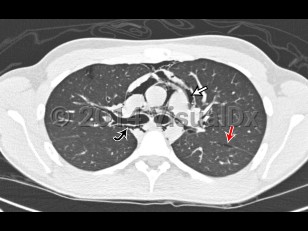

Pneumomediastinum is the presence of air in the mediastinum. It is caused by injury, most often esophageal or intestinal perforation. It is also seen as a result of aggressive bag-valve mask ventilation during resuscitation and intubation as well as a result of barotrauma in intubated patients.